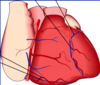

Q

CN:

What is a coronary bypass graft?

A

A procedure to bypass a blocked section of a coronary artery and to deliver oxygen to the heart